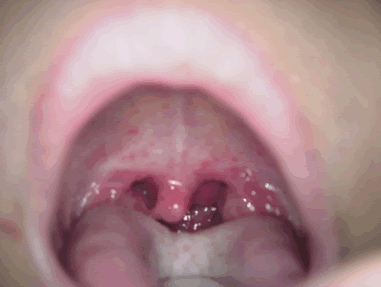

ヘルパンギーナ。